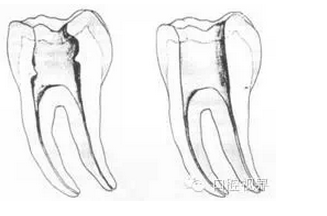

1. 正常開髓孔的位置和大小

左圖為正常開髓孔的大小和位置。左邊圖為下顎,右邊圖為上顎。